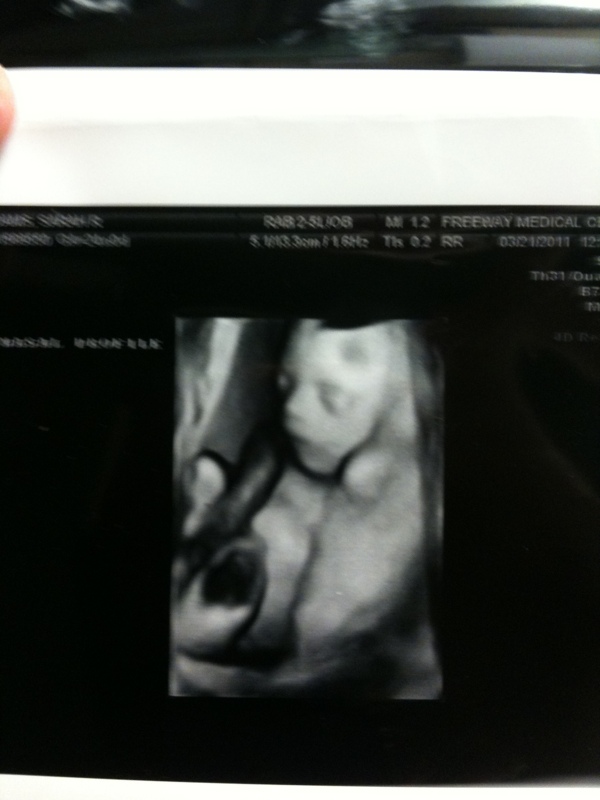

After leaving Cornerstone I headed to Freeway to meet Taylor for my big ultrasound. I was nervous but Taylor has a special way of keeping me calm. He is my rock. The ultrasound went really well. The cyst on Burke's brain is gone! Isn't that awesome news! His kidney's are still a little dilated but nothing the doctor seemed too concerned about. He said Burke might have to take an antibiotic when he is born which is wonderful news. Praise God! Below are some pictures we got from his ultrasound. Sweet baby boy is growing and we can't wait to meet him.